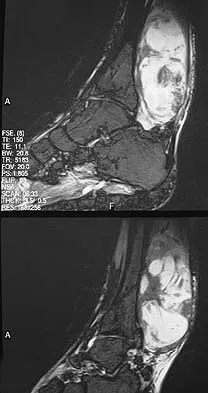

Question 67 High Yield

A 32-year-old laborer reports left ankle pain and deformity. History reveals that he sustained a left ankle fracture 2 years ago and was treated with closed reduction and casting. Radiographs are shown in Figures 25a through 25c. What is the most appropriate management?

Detailed Explanation

Corrective osteotomy of fibular malunions, with appropriate lengthening, even in the presence of early arthritis, has been shown to decrease ankle pain and increase stability. Reduction and bone grafting of the medial malleolar nonunion is also needed. There is no evidence supporting the use of intra-articular steroids or hyaluronic acid in the ankle joint. Lateral talar displacement of even 1 mm has been reproducibly shown to decrease tibiotalar contact by 40% to 42%, causing a predisposition to arthritis. Weber D, Friederich NF, Muller W: Lengthening osteotomy of the fibula for post-traumatic malunion: Indication, technique and results. Int Orthop 1998;22:149-152. Lloyd J, Elsayed S, Hariharan K, et al: Revisiting the concept of talar shift in ankle fractures. Foot Ankle Int 2006;27:793-796. Offierski CM, Graham JD, Hall JH, et al: Later revision of fibular malunion in ankle fractures. Clin Orthop Relat Res 1982;171:145-149.